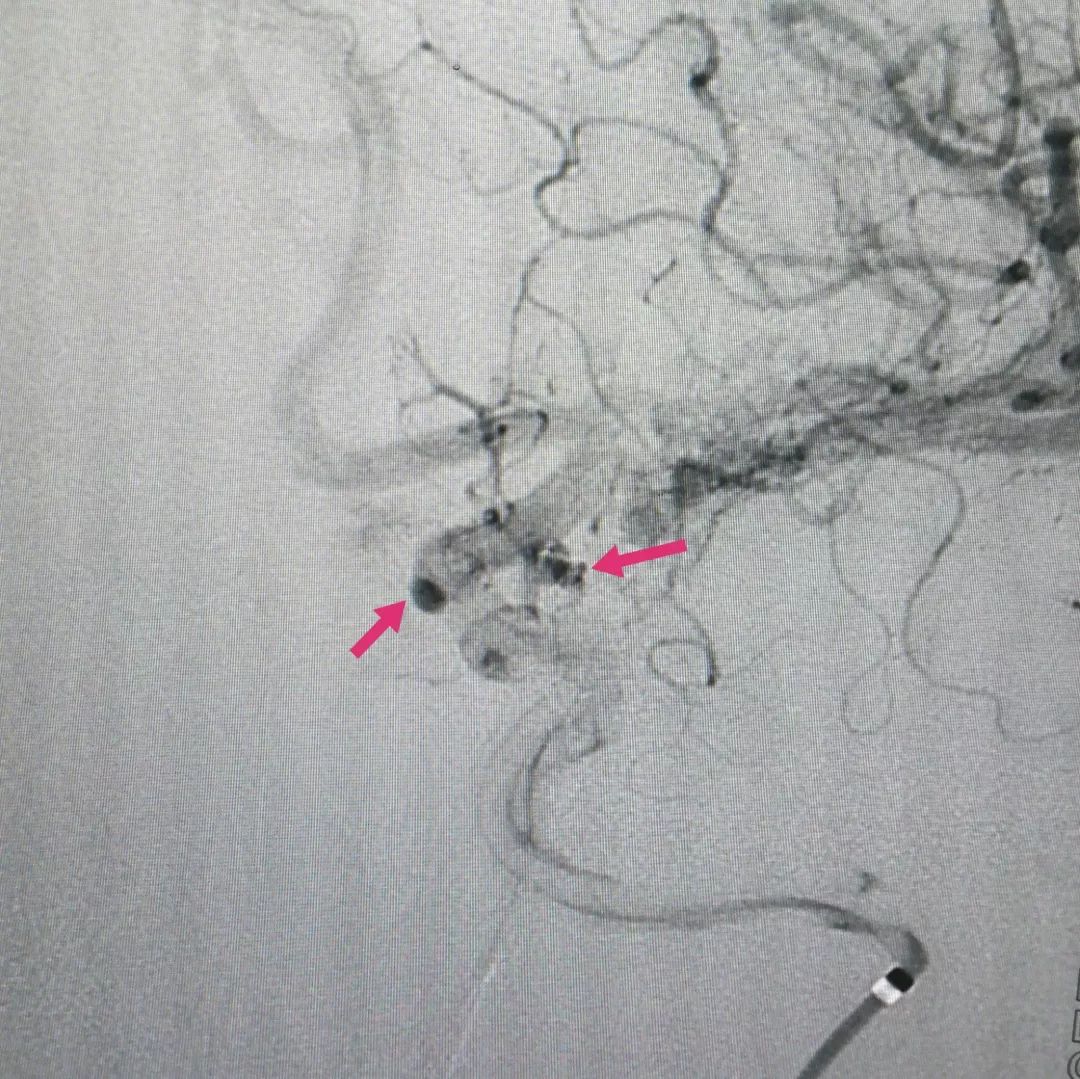

患者中年女性,头痛头晕检查发现颅内多发动脉瘤(下图绿箭头),一个位于后交通段,一个位于眼动脉段。

而且在较大的动脉瘤腔还长出了一根重要动脉血管-后交通动脉(红箭头),该动脉一旦闭塞可能会导致偏瘫甚至昏迷不醒

手术后复查脑血管造影可见动脉瘤已经大部分再显影,残余瘤腔内造影剂明显滞留(下图),提示动脉瘤内血流缓慢,而这就是密网支架的独特效果。根据冬雷脑科医生集团的临床经验,微小动脉瘤一般半年后的完全治愈率是100%